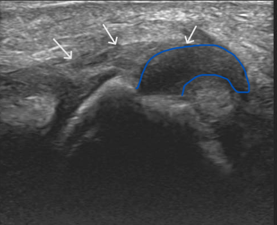

Long axis ultrasound of the thumb at the level of the metacarpophalangeal joint.

The white arrows demonstrate the adductor pollicis aponeurosis. The blue trace outlines the torn and retracted ULC from the base of the proximal phalanx. It has flipped proximally – lying superficial to the aponeurosis.